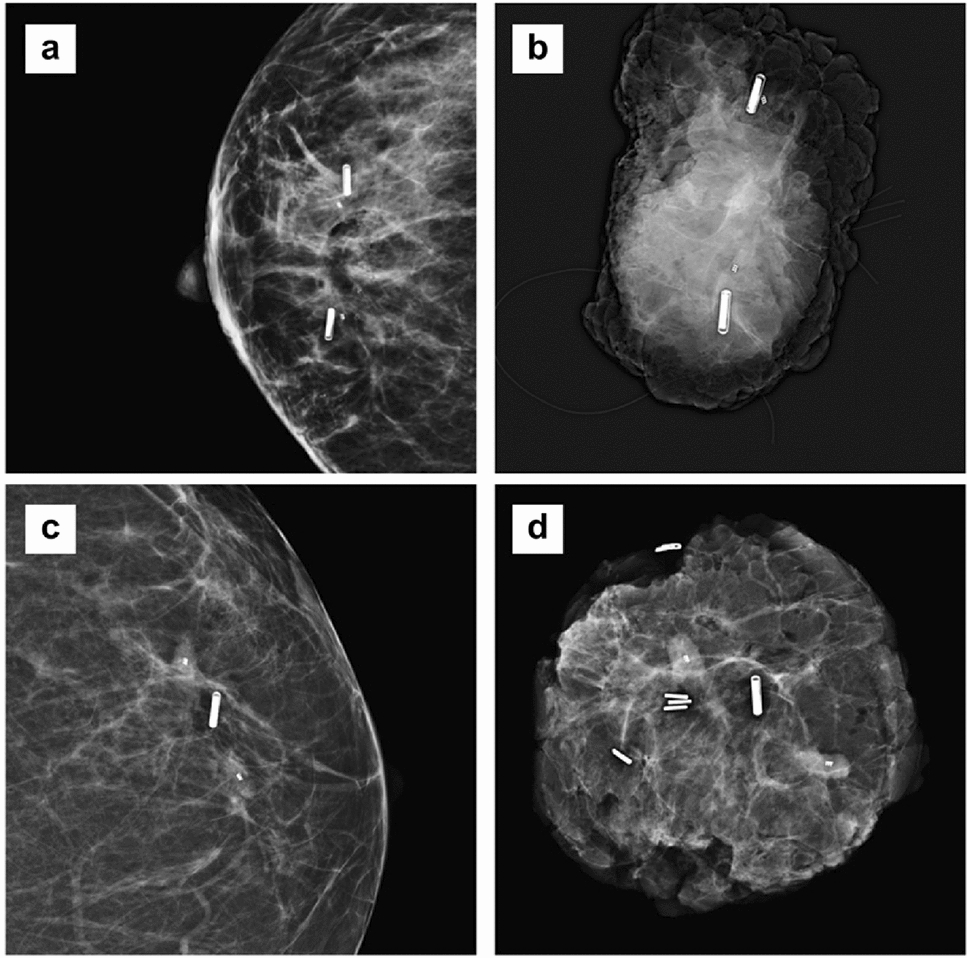

Experience of the radiologists with respect to the RFID placement is illustrated in Fig. 3 Radiologists were positive about the RFID tag visibility on ultrasound and easy handling of the needle-applicator. However, they experienced difficulty penetrating through dense glandular tissue and solid tumour tissue which led to repeated punctures and manoeuvring of the needle-applicator through the tissue. In relation to this, they assessed the size of the RFID tag and accompanying 12-gauge needle-applicator as large, necessitating local anaesthesia and increasing the risk of bleeding/hematoma. For these reasons, radiologists in one study centre (Diakonessenhuis Utrecht) preferred the radioactive seed procedure over RFID localization leading to premature termination of the study at this site. In response, the needle-applicator was modified to allow for a smooth penetration of dense breast tissue and solid tumours. The modified needle-applicator, implemented after the first 50 procedures, led to an improved user satisfaction (Fig. 3) in the remaining site (MST). In addition, there was an improvement of the successful placement rate from 90% (45 out of 50) to 98% (49 out of 50). However, a substantial learning curve for the radiologists was observed (Fig. 3). Specifically, the radiologists with few or infrequent procedures had a preference towards RSL, whilst radiologists had no preference between RSL/WL and RFID seed after 10 RFID procedures and following frequent placements (monthly). In two patients, two RFID tags were placed to delineate an area of interest. In one patient with multifocal invasive carcinoma an area of 3.2 cm was delineated. In the other case two tags delineated an area of 4 cm DCIS grade 3. In one patient 1 RFID tag was placed between two areas of DCIS grade 3, which were marked with a biopsy clip marker. (Fig. 4).

Fig. 4

A Postplacement mammography (CC-view) of a patient with 2 RFID tags to delineate an area of multifocal breast cancer after NAC; B the corresponding specimen radiography (Trident, Hologic) after surgery, with the 2 RFID tag, 2 biopsy clip markers and marking sutures in situ; C postplacement mammography (CC-view) of a patient with 1 RFID tag in-between 2 clip markers which both designate an area of microcalcifications; D the corresponding specimen radiography (Trident, Hologic) after surgery, with the RFID tag, 2 biopsy clip markers and multiple specimen clips in situ